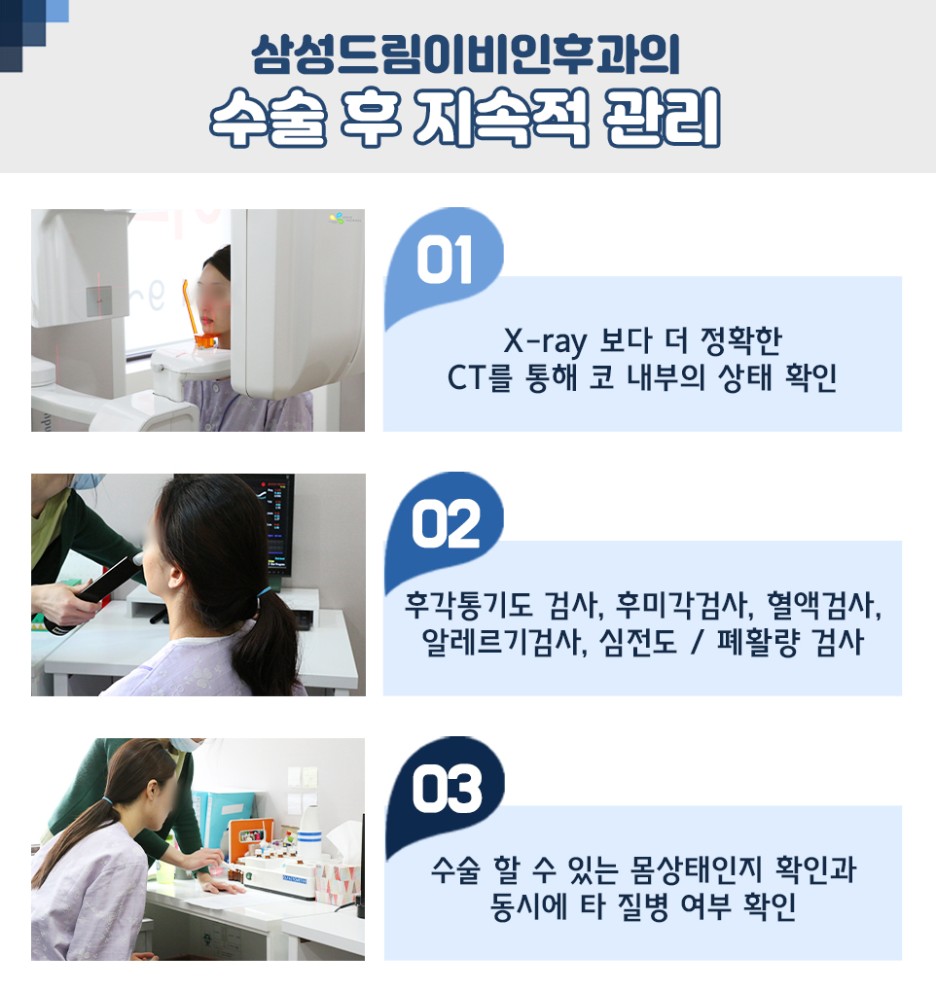

삶의 질을 계속 망가뜨리는 부분이 많아서 충농증 수술 후 결과를 다양하게 확인하는 것도 중요하지만 이런 경우 3D-CT 같은 장비에서 어느 정도 문제가 있는지 확인하고 꼼꼼히 이를 체크하는 것이 우선적이라고 할 수 있습니다. 염증이나 주변 조직을 보고 개개인에 맞는 진료를 하는 것이 올바른 선택이었습니다.

코라는 부위는 민감한 부위였고, 부빙동이라는 부위는 코 내부 안쪽에 위치하고 있어 보다 꼼꼼한 관리가 적용되어야 했습니다. 주위의 신경과 점막, 지지대까지 고려하여 면밀히 조사하는 곳을 선택하는 것이 올바른 판단이었습니다.

저희 병원에서는 비염과 축농증에 대한 세심한 관리 프로그램을 준비하고 있기 때문에 걱정도 줄일 수 있었습니다. 축농증 치료는 복잡한 코 내부 구조를 의료진이 확인하고 집도하는데 정교한 장비가 요구됐는데요. 축농증 상황에 맞게 가느다란 장비를 사용하여 보다 세밀하게 코 구조를 체크하여 진행하고 있기 때문에 보다 만족감 높은 결과를 만들 수 있었습니다. 더욱이 염증이 있는 부분만 선택적으로 치료해 짧은 시간에 얻은 결과를 기대할 수 있었습니다.